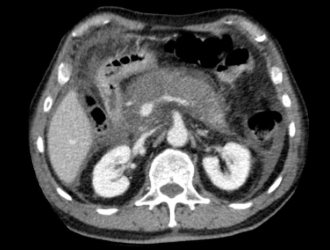

- КТ или МРТ;

При проявлении симптомов острого панкреатита необходимо провести дифференциальную диагностику с острым аппендицитом, кишечной непроходимостью, желудочно-кишечным кровотечением и обострением язвенной болезни. Клиническая картина состояния здоровья пациента составляется на основе жалоб, внешнего осмотра, а также результатов лабораторных и инструментальных исследований.

Инструментальная и лабораторная диагностика являются неотъемлемой частью процесса обследования пациента. Общий и биохимический анализ крови назначается в обязательном порядке. Дополнительно проводятся специальные индикаторные тесты. Процедуры инструментальной диагностики подбираются с учетом общего состояния пациента.